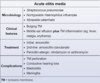

diagnostic criteria for Acute Otitis Media -2

________________

Which organisms cause AOM? -3

BULGING TM + [Middle Ear effusion with TM inflammation (fever/otalgia/erythema)]

________________

STREP PNEUMO = [HFLU NONTYPEABLE**] >> moraxella

________________

** also causes otitis conjunctivitis syndrome

Prophylactic abx tx and tympanostomy tube ⬇︎ [recurrent AOM],

and are recommended for which 4 patient groups?

[≥ 3 AOM in 6 mo] or

[≥4 AOM in 12 mo] or

[craniofacial DO] or

[neurodevelopmental DO = speech/hearing ❌]